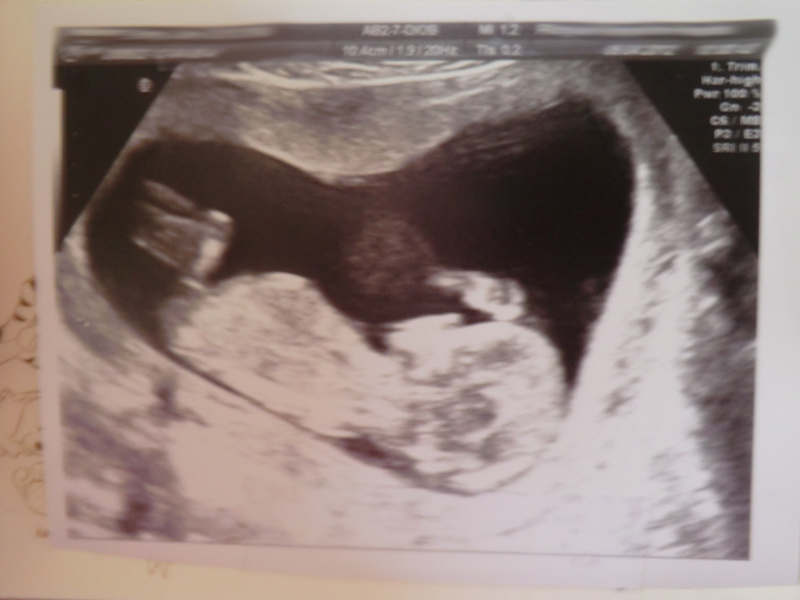

My 12+6 scan pics!

Does the top one look boyish?

Baby had his/her legs crossed the entire time, and kept bringing it up to their chest... also the angle wasn't quite right so it was hard to see a nub and I can't be definite I saw one at all during the scan (saw it so easily with DS) although it looks like there might be a nub in these pictures.

If that's the nub I'm seeing, it definitely looks girly to me!!! :cheer:

First pic makes me think boy, second pic makes me think girl.

however the skull looks very girly to me and I still have a gut feeling you have a girl growing in there so I will stick with

If that's the nub we are seeing, I'm guessing: :DD:

The last pic looks girly to me.